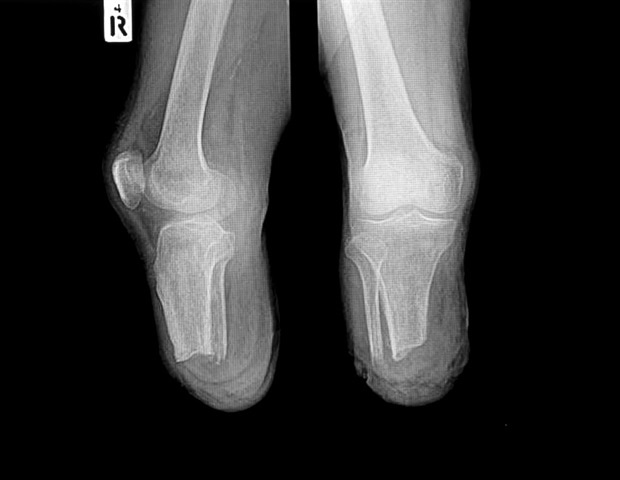

Οι ερευνητές αποδίδουν αυτή την αύξηση κυρίως στην αυξανόμενη συχνότητα διαβήτη και περιφερικής αρτηριακής νόσου (PAD), δύο χρόνιες καταστάσεις που συχνά οδηγούν σε ακρωτηριασμούς στα κάτω άκρα. Δυστυχώς, πολλοί ασθενείς με διαβήτη ή PAD φτάνουν στο νοσοκομείο με σοβαρές πληγές ή λοιμώξεις, όταν η κατάσταση τους έχει προχωρήσει τόσο πολύ που η μόνη επιλογή είναι ο ακρωτηριασμός.

Δραματική αύξηση στους ασθενείς με διαβήτη και PAD

Η Δρ. Maggie Reilly, επικεφαλής συγγραφέας της μελέτης και κάτοικος αγγειοχειρουργικής στο McGaw Medical Center του Northwestern University, τόνισε ότι οι ασθενείς με διαβήτη και PAD παρουσίασαν την μεγαλύτερη αύξηση στους ακρωτηριασμούς. Παρά τη μείωση του καπνίσματος και τις βελτιώσεις στις ιατρικές θεραπείες, όπως η χρήση στατίνων, αυτές οι θετικές εξελίξεις δεν επαρκούν για να αντισταθμίσουν την ταχεία αύξηση των περιπτώσεων διαβήτη και PAD.